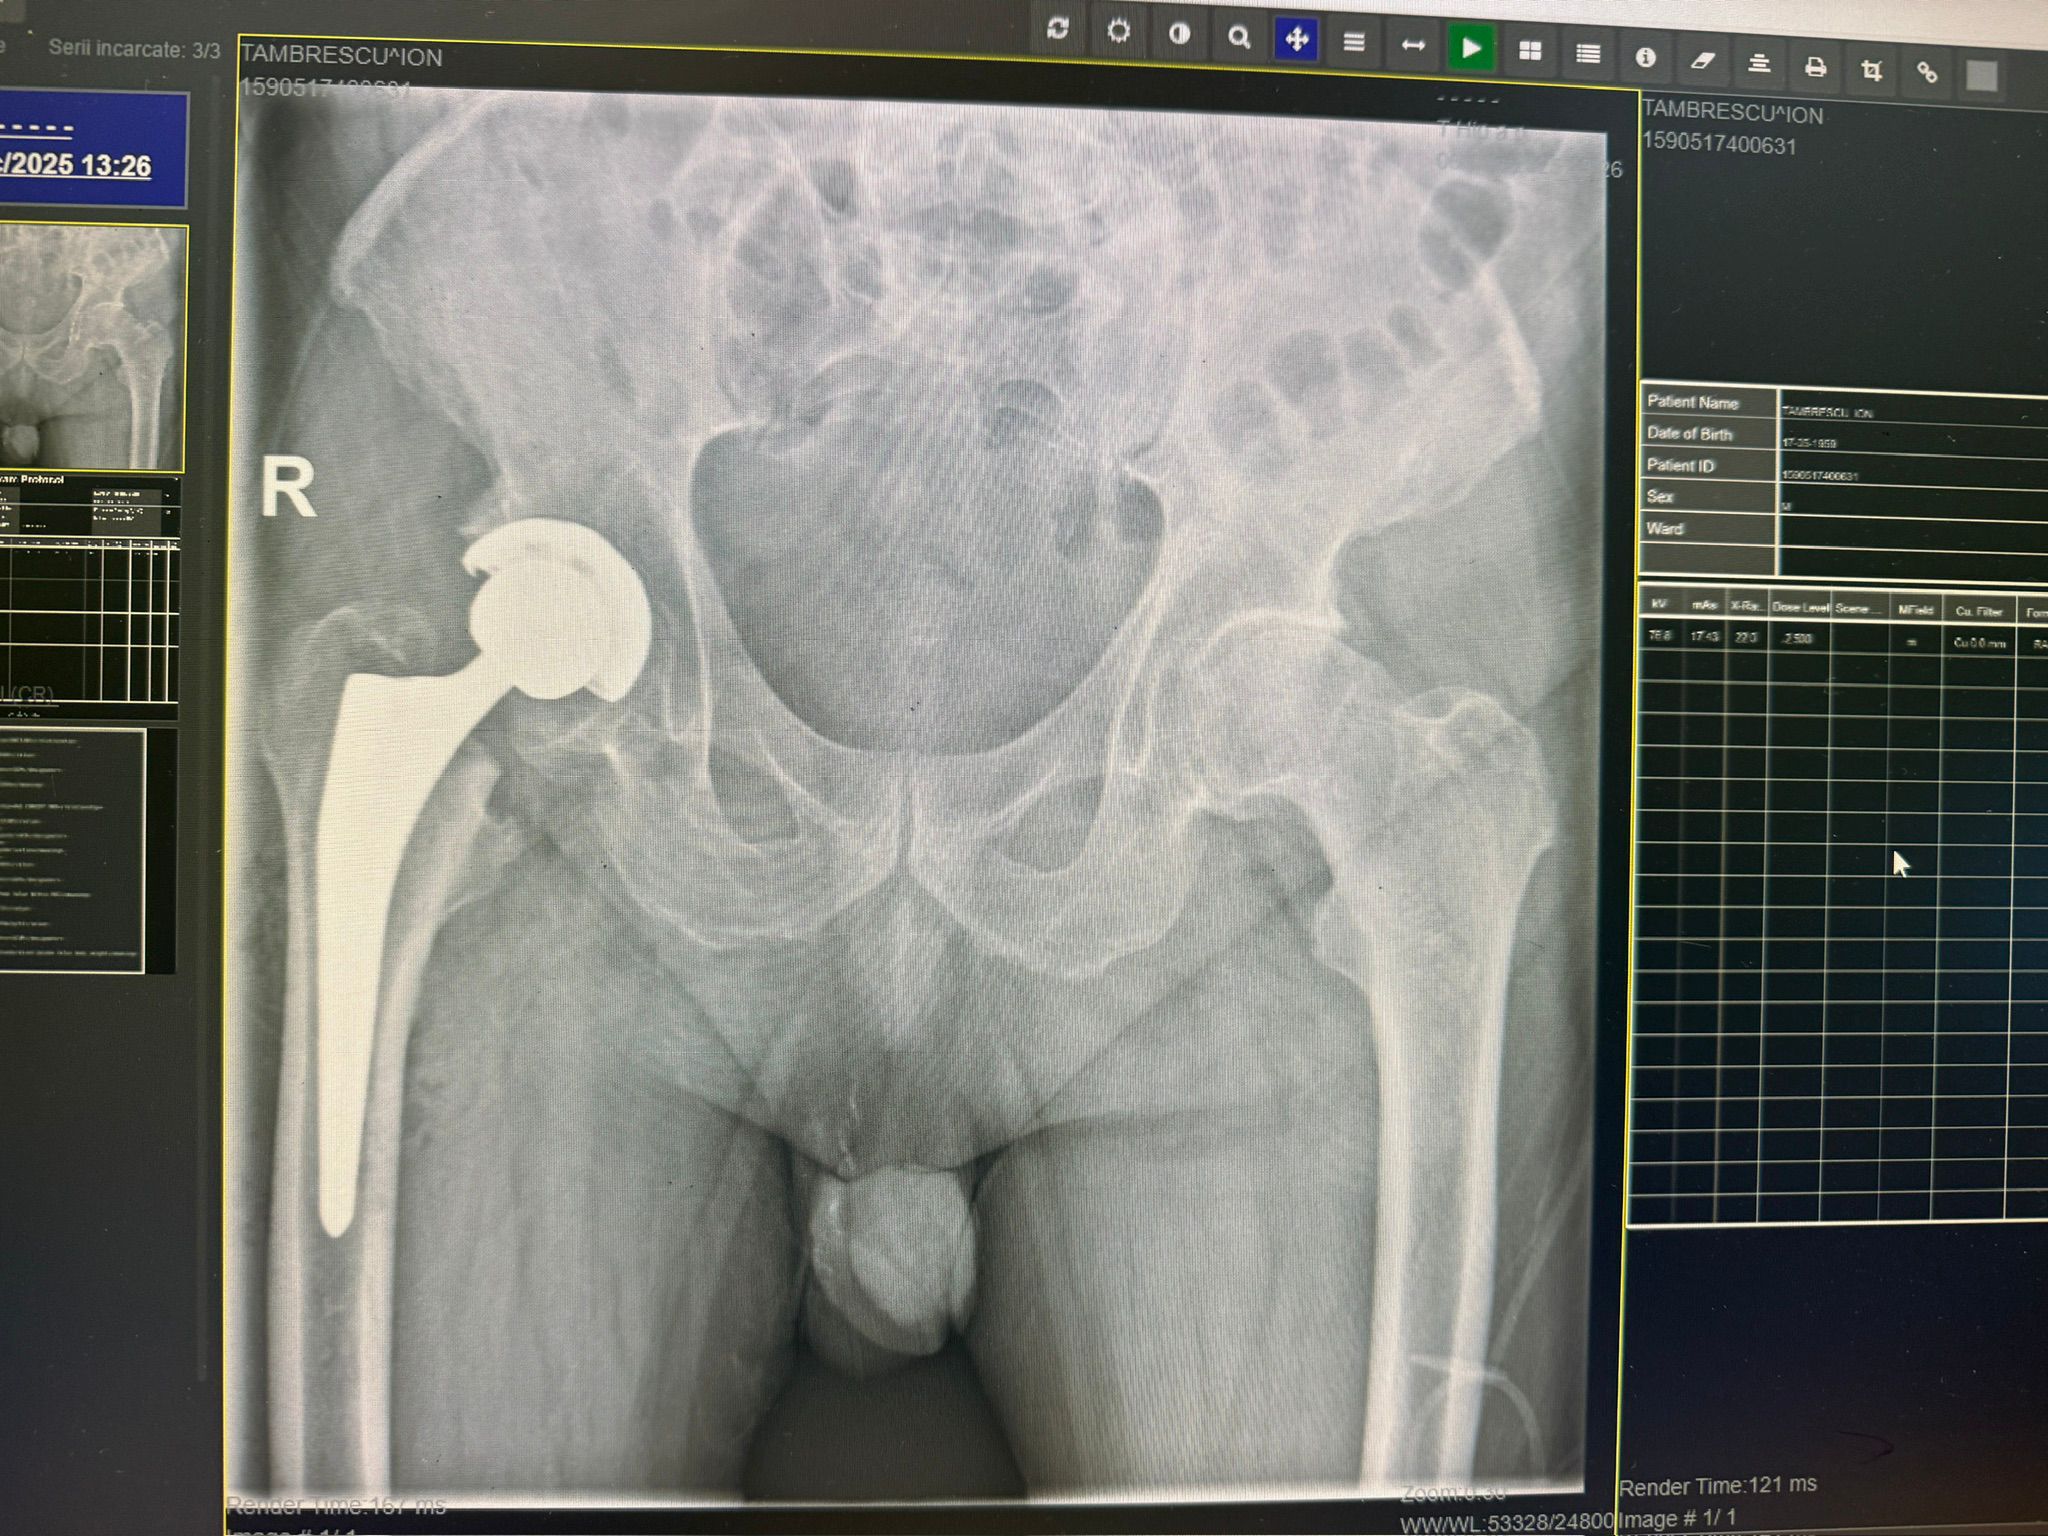

Imagini Clinice